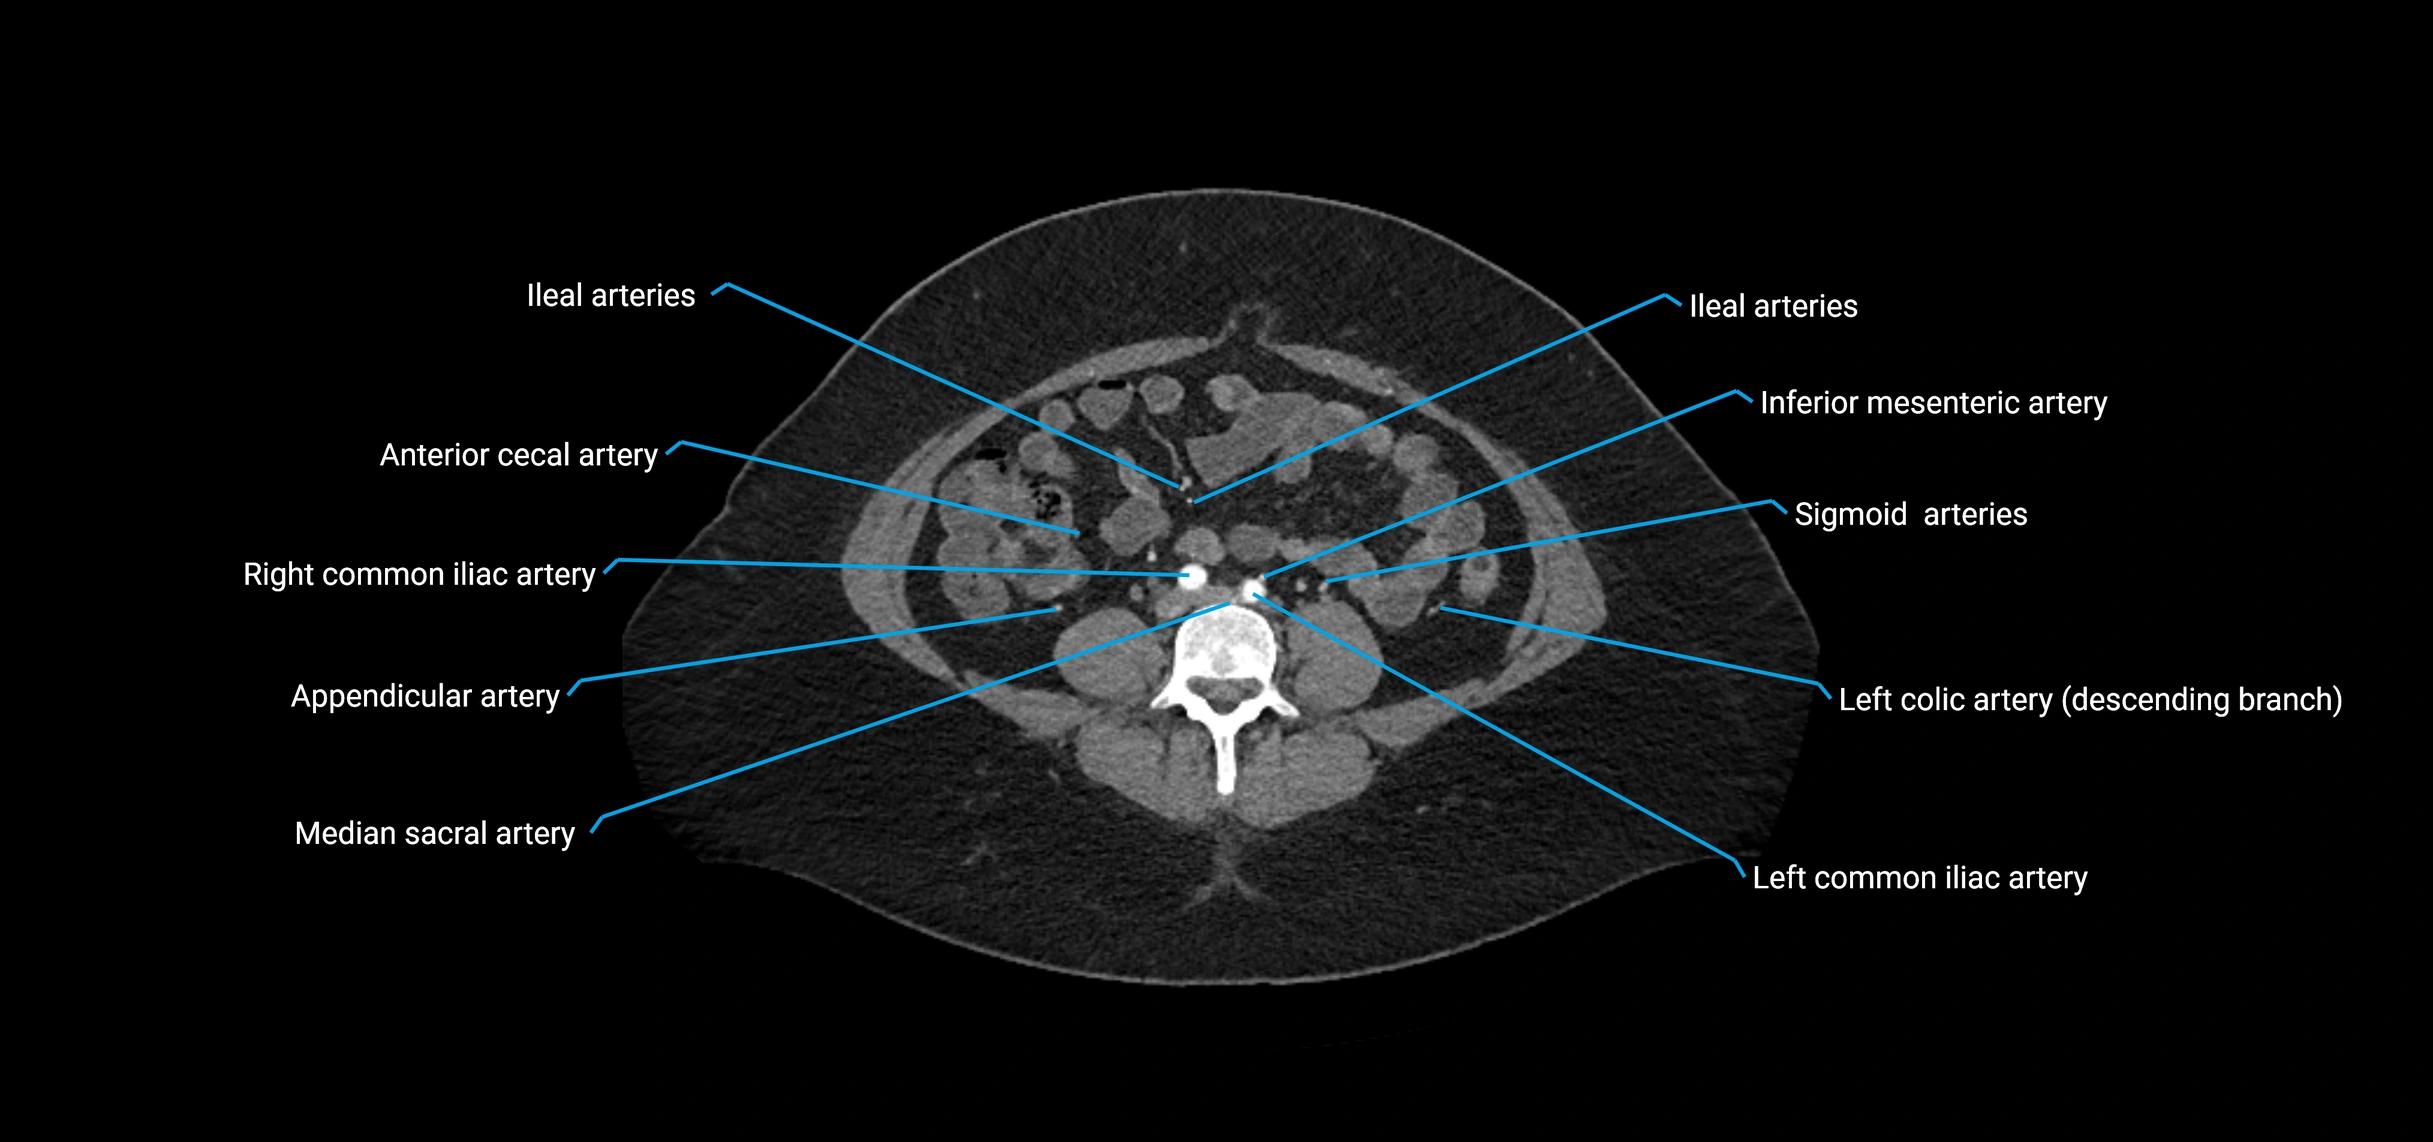

CT Appearance

Non-contrast CT:

• Appears as a tubular soft tissue structure anterior to vertebral bodies

• Calcified atherosclerotic plaques appear as hyperdense foci along the wall

• Useful for screening abdominal aortic aneurysm (AAA) size and mural calcification

Contrast-enhanced CT (CTA):

• Gold standard for abdominal aortic imaging

• Provides excellent detail of lumen, wall, aneurysm, thrombus, and branch vessels

• Multiplanar and 3D reconstructions help in aneurysm measurement, stent graft planning, and dissection evaluation

• Detects acute rupture, traumatic injury, or occlusion with high sensitivity

CT images

image